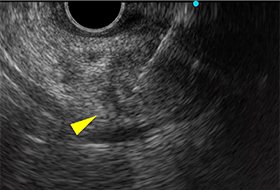

膵尾部分枝型IPMN

超音波内視鏡のみでのう胞内結節を指摘